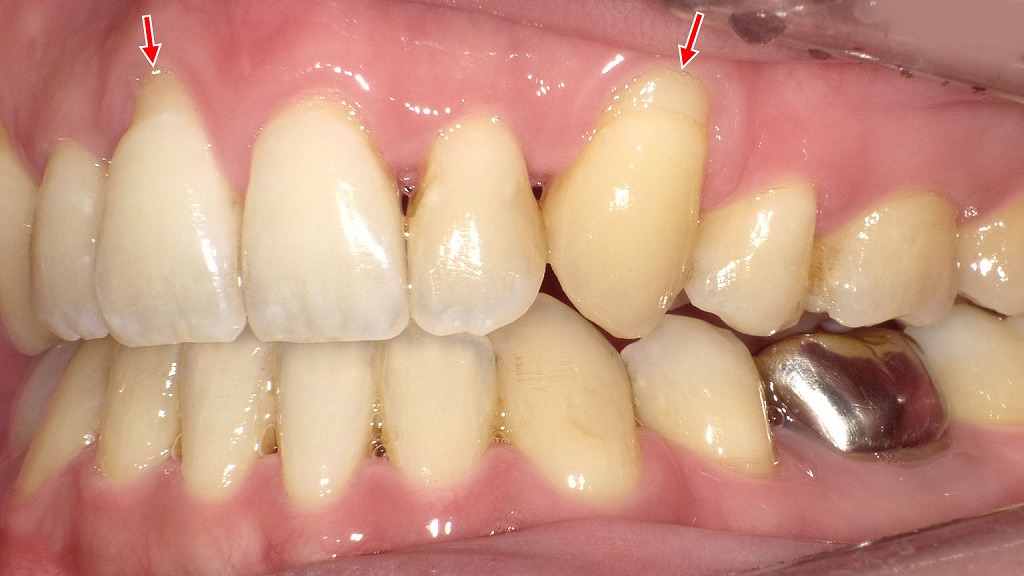

◆炎症が強まり、触れただけで出血する状態:右側面

右側面の画像では、矢印部の歯肉に明らかな自然出血が認められます。

これは歯肉炎が進行し、わずかな刺激でも血管が破れやすくなっているサインです。

側面の歯にもプラークや着色が付着し、歯肉との境目に汚れがたまりやすい状態が続いているため、炎症がさらに強まっています。

その結果、

- 歯茎がジンジンする

- 歯ブラシでしみる

- 噛んだときに違和感を感じる

などの症状が出やすくなります。